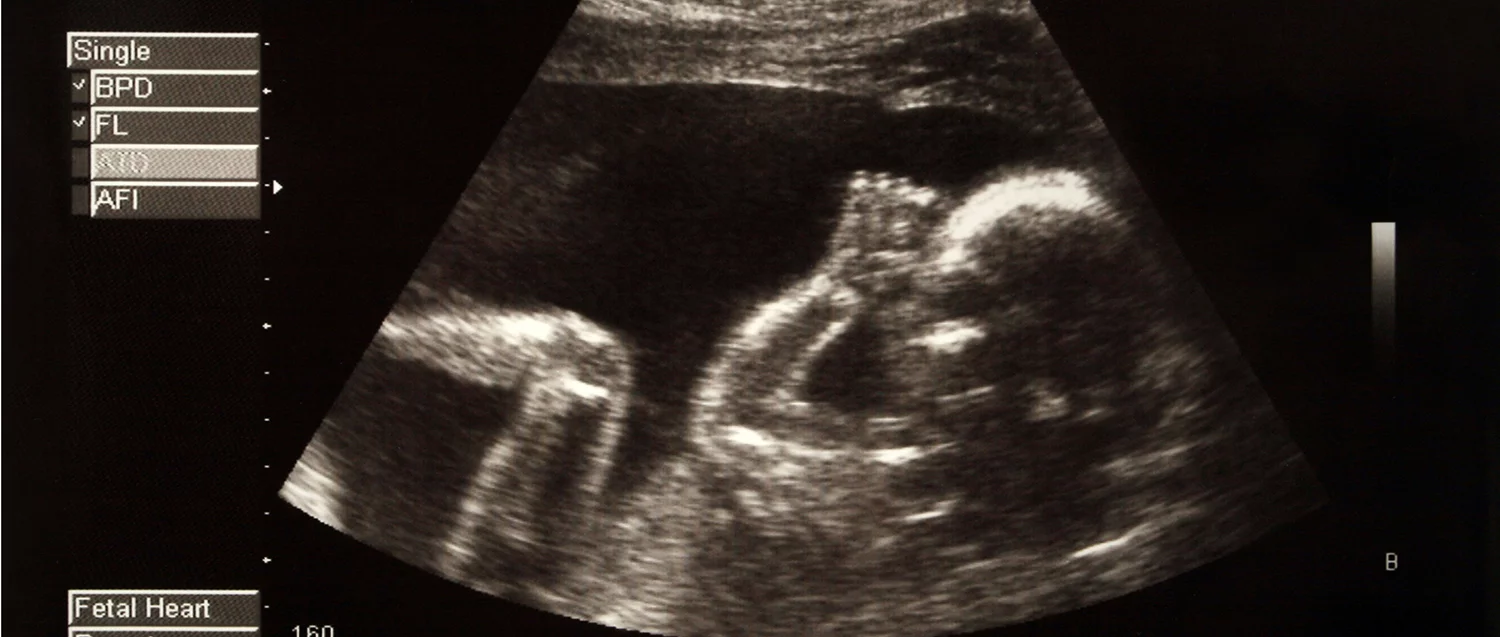

L'échographie intra-vaginale pour les premiers mois et l'échographie abdominale pour les suivants et le moyen, par ultrasons, d'observer le bébé pendant la grossesse. Anomalies, développement, etc.